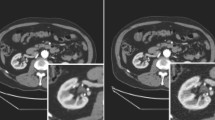

Deep learning reconstruction (DLR) is a new reconstruction method; it introduces deep convolutional neural networks into the reconstruction flow. This study was conducted in order to examine the clinical applicability of abdominal ultra-high-resolution CT (U-HRCT) exams reconstructed with a new DLR in comparison to hybrid and model-based iterative reconstruction (hybrid-IR, MBIR).

The image noise was significantly lower and the CNR was significantly higher on DLR than hybrid-IR and MBIR images (p < 0.01). DLR images received the highest and MBIR images the lowest scores for overall image quality.

DLR improved the quality of abdominal U-HRCT images.

• Image noise and overall image quality for hepatic ultra-high-resolution CT images improved with deep learning reconstruction as compared to hybrid- and model-based iterative reconstruction.